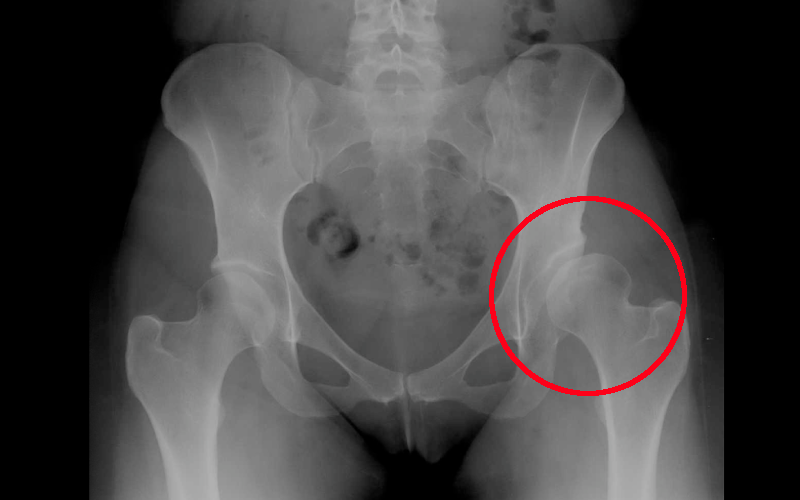

La protesi d'anca viene impiantata quando sia presente una importante sintomatologia dolorosa all'articolazione coxo-femorale, in presenza di immagini radiologiche che mostrino la presenza di:

- displasia: condizione per la quale lo sviluppo dell'articolazione ha subito delle alterazioni per cui la testa del femore si trova in posizione diversa da quella normale e l'acetabolo ha una conformazione non in grado di accogliere la testa femorale.

Fai il paragone con l'anca controlaterale

- necrosi: condizione per la quale alcune aree della testa del femore si necrotizzano e si afflosciano determinando la perdita della struttura spongiosa e il supporto alla cartilagine articolare.